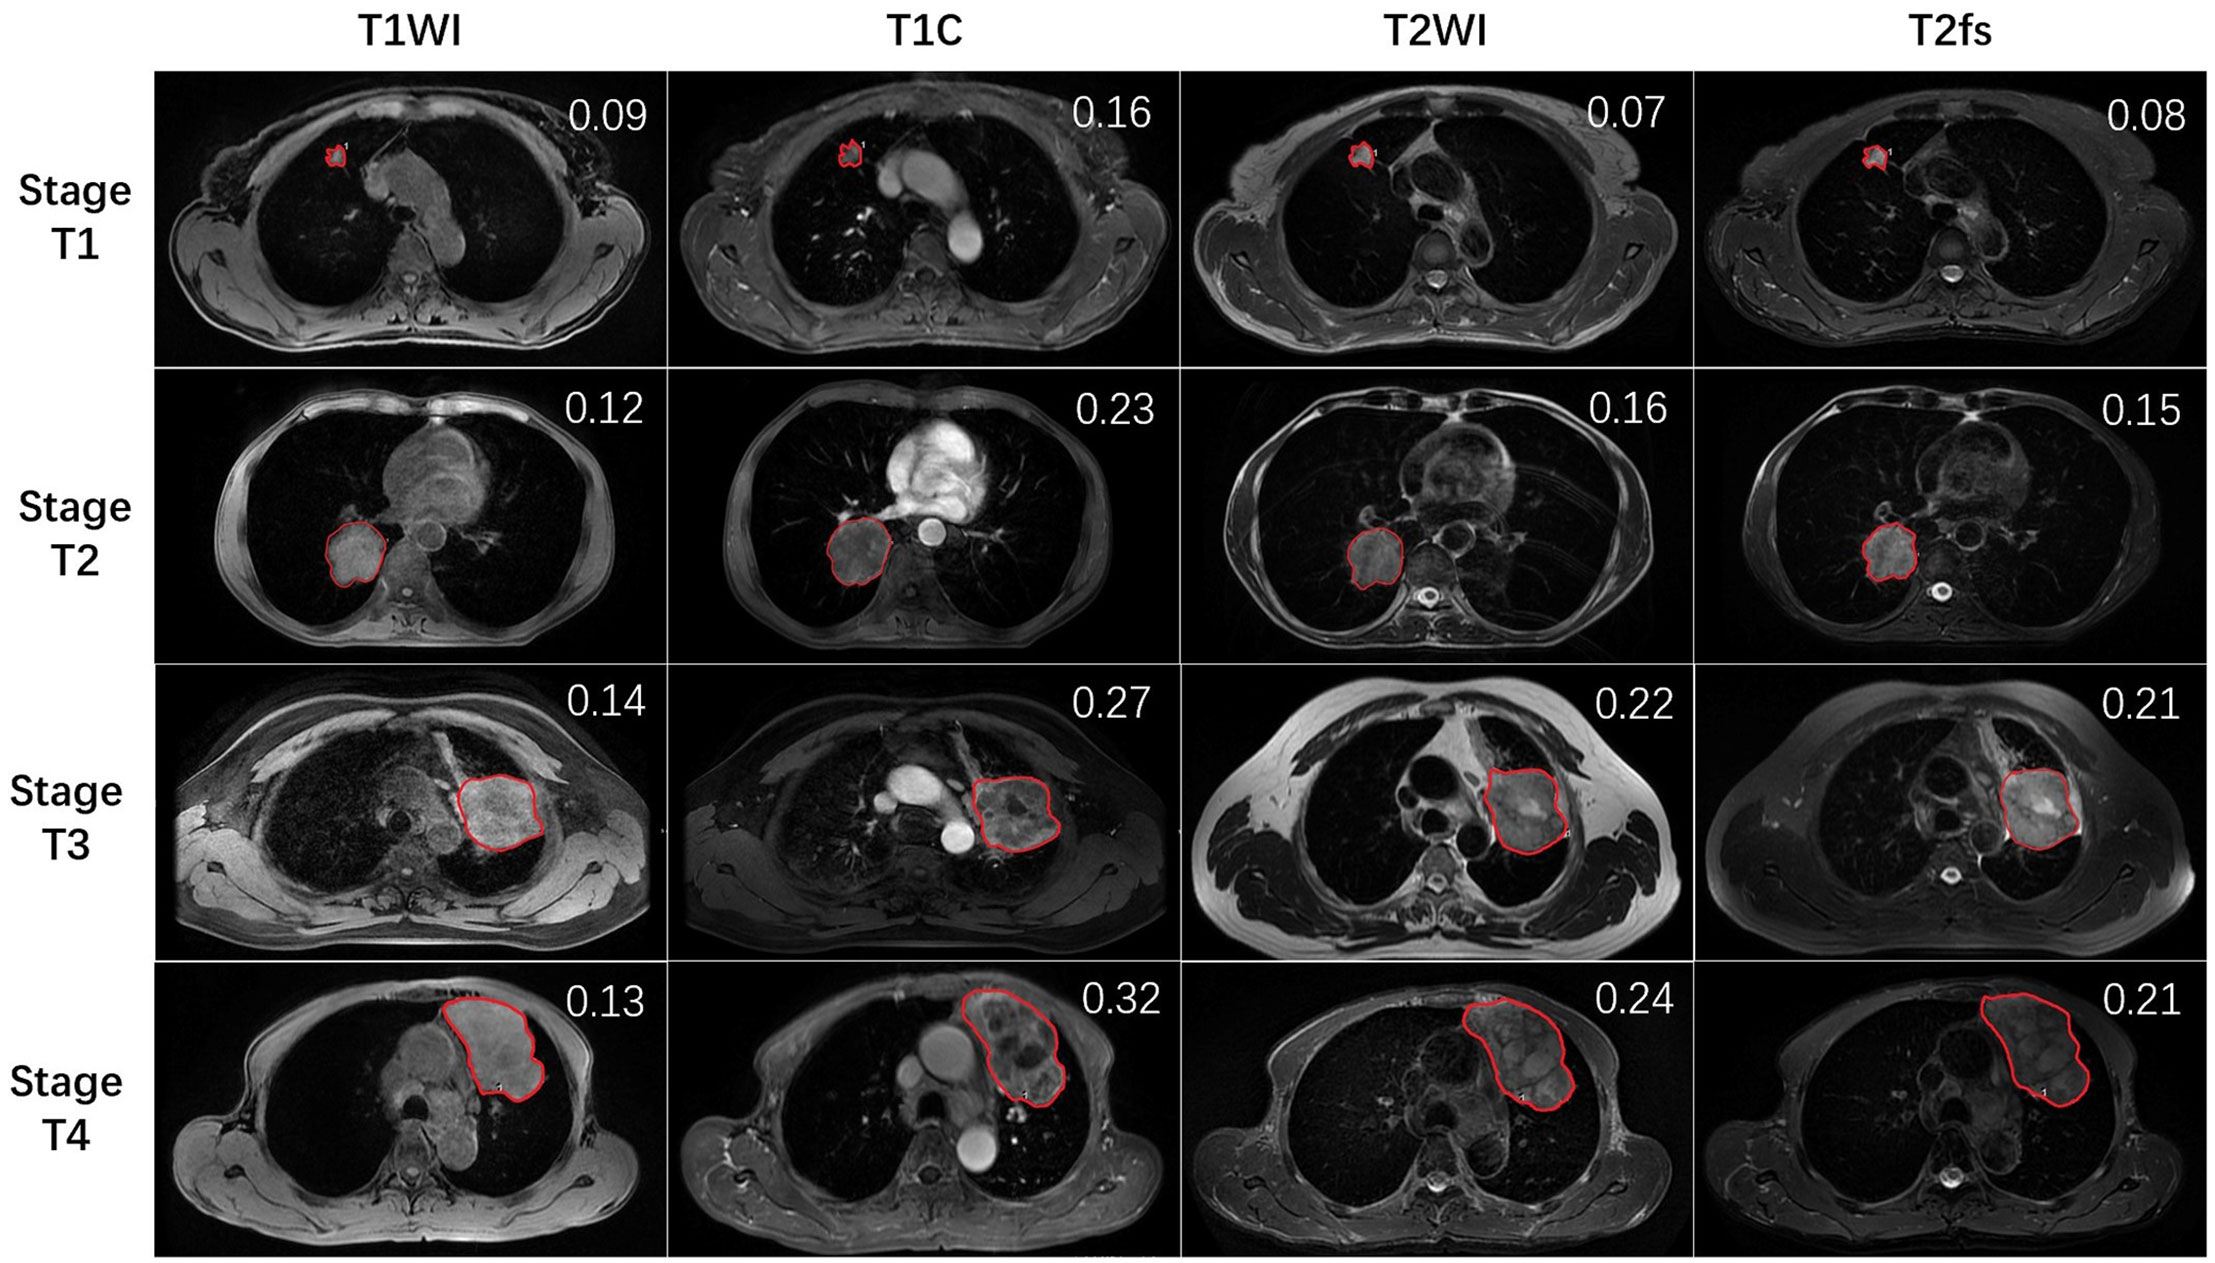

最新入荷 Imaging Features of Juvenile Xanthogranuloma of the 医学一般